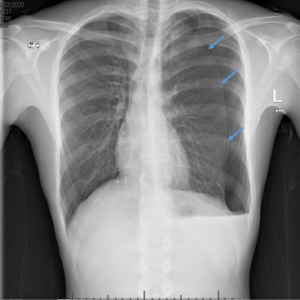

Bilateral pneumothorax

Figure 1: Bilateral pneumothorax - blue arrows show lung edge